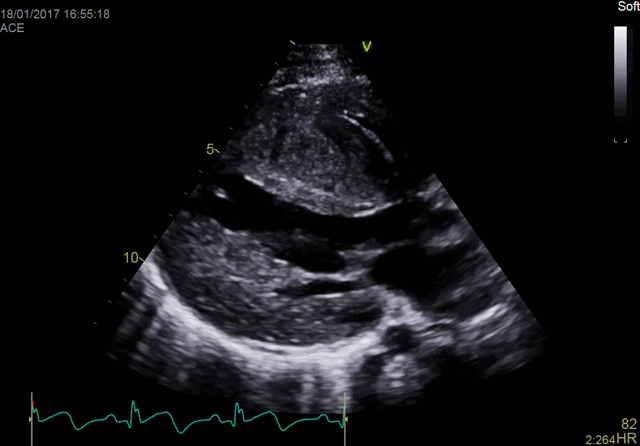

One patient, one probe The new one-probe adult 4D TTE solution on the Vivid™ E95 provides an excellent ergonomic workflow solution with uncompromised 2D, 4D, color and Doppler image quality performance at ultra-high volume rates - all with a single probe. This allows for complete and comprehensive diagnosis with one probe and avoids switching of probes, thereby reducing exam time and helping you move swiftly through your work with minimal muscular stress and strain on the operator.